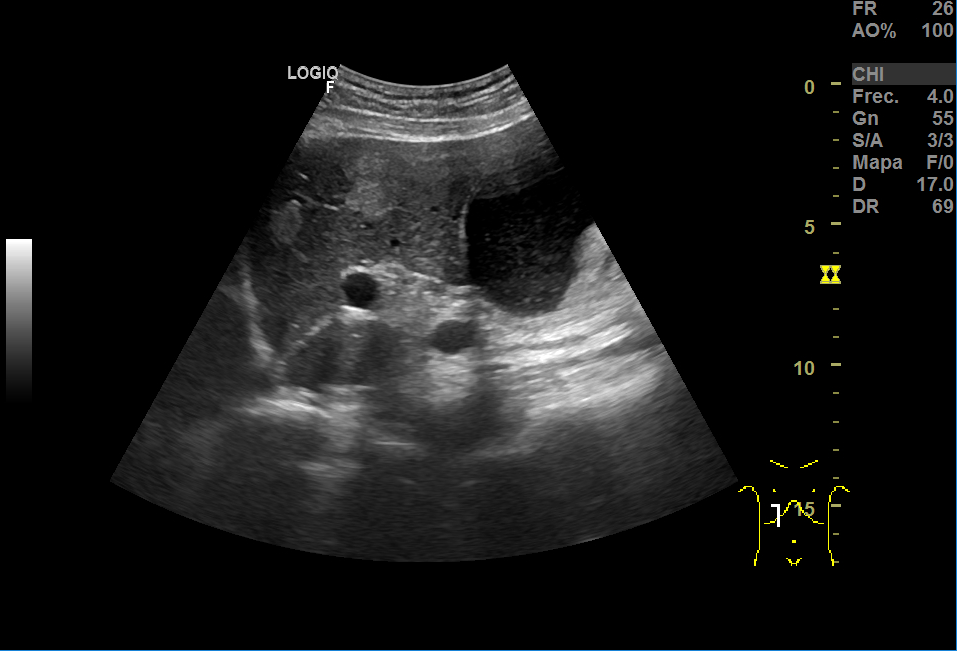

En la ecografía, a nivel hepático, vimos unas imágenes hiperecoicas redondeadas hipervascularizadas: una de aproximadamente 5 cm de diámetro y otra de 3cm, sospechosas de LOEs (lesiones ocupantes de espacio).

El aspecto de los hemangiomas hepáticos en la ecografía son lesiones de pequeño tamaño (inferior a 30 mm), hiperecoicas, bien delimitadas, homogéneas, con refuerzo acústico posterior y sin captación en el estudio Doppler. En cambio, el aspecto ecográfico atípico como el de nuestro caso: mayor tamaño, heteroecoico con zona central hipoecoica y límites irregulares o mal definidos, requiere de otras técnicas.

El ecógrafo del centro de salud es una herramienta muy útil que nos ayuda al diagnóstico, pero no nos da el definitivo; para ello, en ocasiones, necesitamos la valoración por Especializada. En este caso, las imágenes hepáticas eran muy sugestivas de LOES tipo metástasis pero la valoración por el Digestivo y la realización de otras pruebas de imagen dieron con el diagnóstico definitivo de hemangiomas.